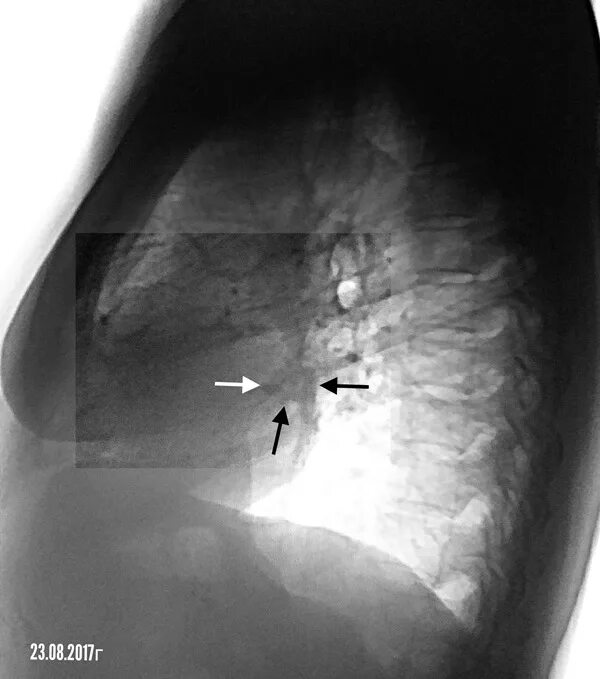

Susp c r